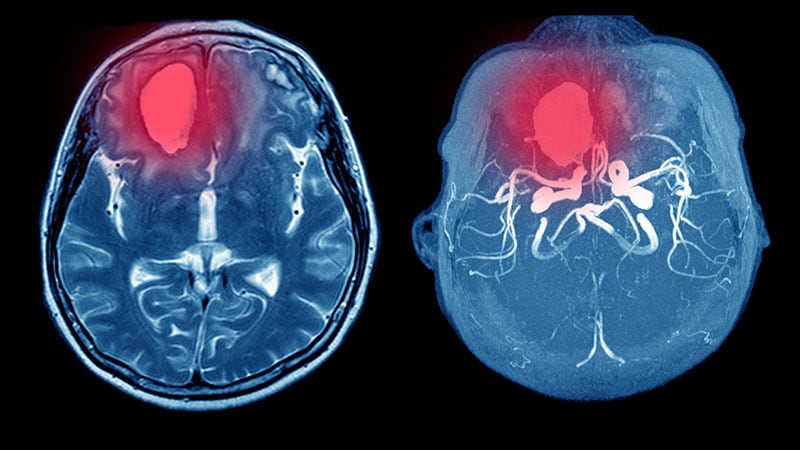

Risk Score May Predict ICH in Anticoagulated Patients

A new tool that uses information found in patients’ medical records could predict risk for intracranial hemorrhage in patients taking anticoagulants, a new study suggests. Medscape Medical News